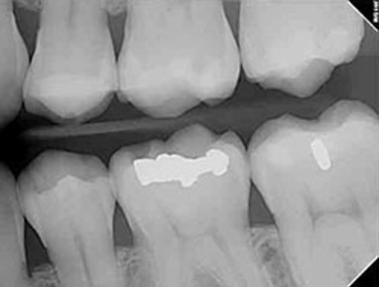

Dental sealants are plastic resins that bond and harden in the deep grooves on  your tooth’s surface. When a tooth is sealed, the tiny grooves become smooth and  are less likely to harbor plaque. With sealants, brushing your teeth becomes easier  and more effective against tooth decay.

Sealants are typically applied to children’s teeth as a preventive measure against  tooth decay after the permanent teeth have erupted. However, adults can also  receive sealants on healthy teeth. It is more common to seal “permanent” teeth  rather than “baby” teeth, but every patient has unique needs, and your dentist will  recommend sealants on a case-by-case basis.

Sealants last from three to five years, but it is fairly common to see adults with  sealants still intact from their childhood. A dental sealant only provides protection  when it is fully intact, so if your sealants come off, let your dentist know, and  schedule an appointment for your teeth to be re-sealed.